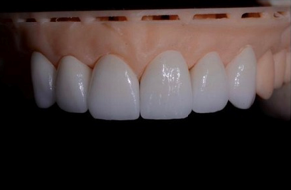

Endodontic Treatment: Challenges and Difficulties of Access Cavities -- Case Series

El Kharroubi Soukaina, Dhoum Sara, Doumari Bouchra, Drouri Sofia, Laslami Kaoutar and El Ouazzani Amal. 22(6): 38-47.